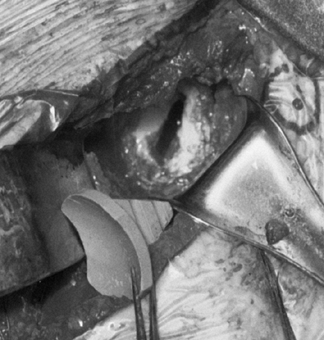

Drill several holes in the remaining subchondral bone for bone cement penetration, and implant the trial glenoid (Fig. 101.36, Fig. 101.37 and Fig. 101.38).

Eliminate any rocking. Several pitfalls exist in seating the trial

glenoid that may result in prominence, rocking, or poor fit of the

glenoid component (Table 101.1).

Figure 101.36. Make multiple small drill holes in the subchondral bone to help anchor the cement.

Figure 101.37.

The trial glenoid is about to be inserted. The trial components for the

standard and metal-backed glenoids are of different colors.

Figure 101.38.

The inserted trial glenoid. This must be seated securely on subchondral

bone. There must not be any anterior and posterior rocking.

Table 101.1. Pitfalls in Seating the Glenoid Component -